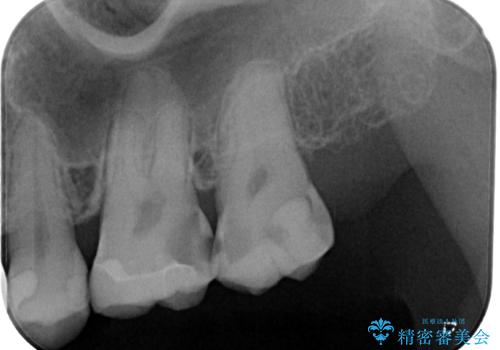

レントゲン写真より、奥歯2本に大きなむし歯があることが分かりました。

手前の歯はセラミックインレーで、奥の歯はオールセラミッククラウンにて治療を行うこととしました。